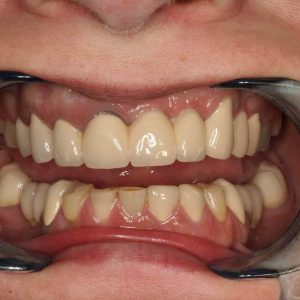

A négy felső frontfog helyén hídpótlás a hiányzó jobb felső nagymetsző miatt. A foghiány miatt az íny negatív kontúrja figyelhető meg

A negatív ínykontúr korrekciója a szájpadból vett kötőszöveti lebennyel és az ideiglenes fogpótlással

Az új híd hat héttel az ínyműtét után készült el